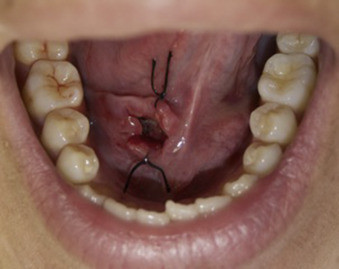

Symptoms of a Ranula in your mouth

A ranula is a fluid collection or cyst that forms in the mouth under the tongue. It is filled with saliva (spit) that has leaked out of a damaged salivary gland. Salivary glands are small structures around the mouth which make saliva. Saliva should drain from these glands directly into the mouth. If one of these glands is damaged then the saliva leaks out into the tissues next to the gland forming a cyst or bubble near the gland. This cyst is called a ranula.

If the ranula stays in the mouth underneath the tongue it is called a simple ranula and if it grows down into the neck under the mouth it is called a plunging ranula.

Ranulas are usually discovered by the patient, the patient’s family, or the patient’s medical caregivers like medical doctors and dentists. It usually is a 2-3 inch diameter painless soft swelling under the tongue or chin that is easy to identify. Occasionally, the fluid collection can hurt a little and sometimes is can spontaneously empty into the mouth only to slowly fill back up in the weeks after it empties. Usually, it just slowly grows in size until it is discovered.